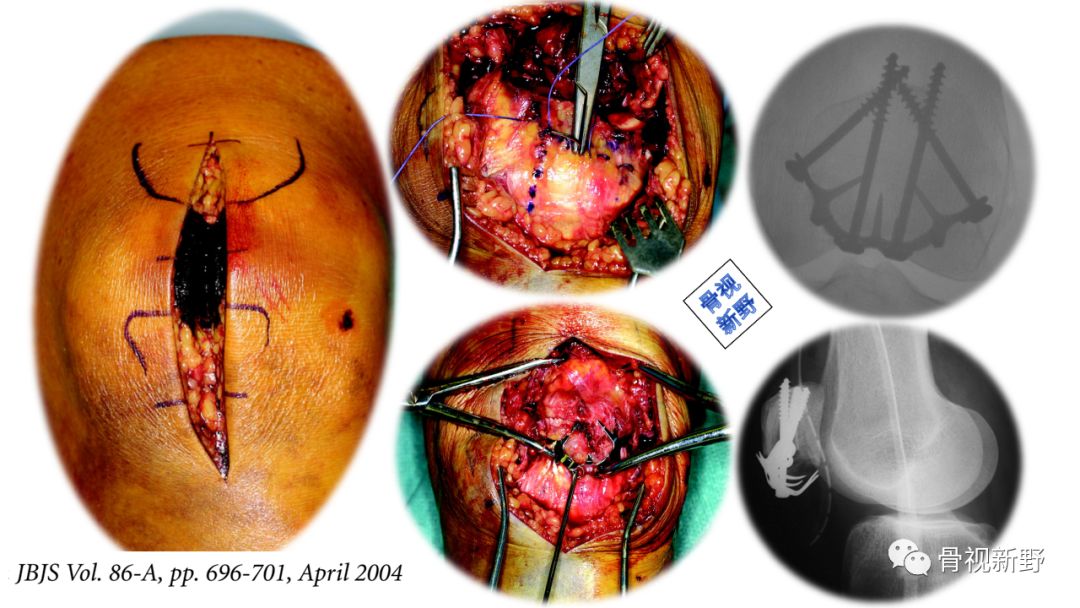

篮状钢板+编织缝合

最早在2006年,Matejcic等用篮状钢板进行髌骨粉碎骨折的固定,获得良好效果。

篮状钢板(basket plate),1988年由Branimir Smiljanic 医生设计,主要用于髌骨下极的粉碎骨折。

篮状钢板有利于收集粉碎骨折块、特别是下极粉碎骨折。该钢板有四个钉孔,半螺纹松钉打入对侧骨块以获得骨碎块间的加压。

术中所见

X光所见